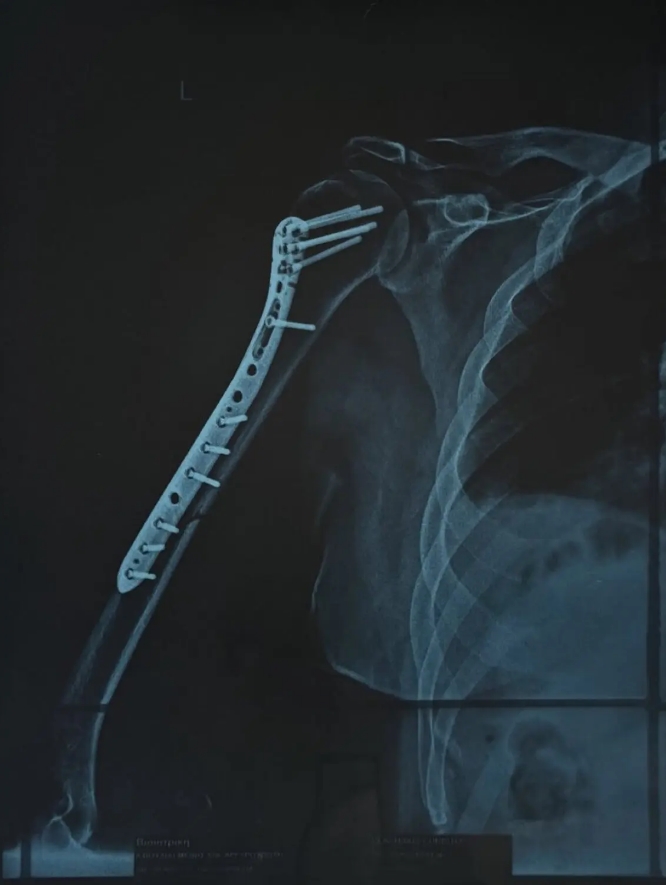

Δύσκολες στιγμές περνά τον τελευταίο καιρό ο Χρήστος Δάντης, καθώς υπέστη κάταγμα στο χέρι και χρειάστηκε να υποβληθεί σε χειρουργική επέμβαση. Ο γνωστός τραγουδιστής και συνθέτης μεταφέρθηκε στην Ευρωκλινική Αθηνών πριν από μία εβδομάδα, με την κατάσταση του χεριού του να είναι ιδιαίτερα επιβαρυμένη, όπως περιέγραψε ο ίδιος.

Μέσα από ανάρτησή του, ο τραγουδιστής θέλησε να ευχαριστήσει δημόσια τον γιατρό που τον χειρούργησε, περιγράφοντας τη δύσκολη κατάσταση στην οποία βρέθηκε πριν μπει στο χειρουργείο: «Όταν θυμάμαι σε ποια κατάσταση μπήκα στην Ευρωκλινική Αθηνών το βράδυ της Πέμπτης, με το χέρι σχεδόν διαλυμένο και σκέφτομαι πόσο γρήγορα θα ανέβω ξανά στη σκηνή την Παρασκευή που έρχεται… μόνο ευγνωμοσύνη μπορώ να νιώσω.

Το «τεράστιο ευχαριστώ» ανήκει στον Χειρουργό Γιώργο Μάζη @shoulderexpert και σε όλο το επιτελείο του, αν και είναι λίγο μπροστά σε αυτό που έκαναν για μένα. Με χειρούργησαν και μου «έδωσαν» πίσω το χέρι μου και τη δυνατότητα να επιστρέψω εκεί που ανήκω: στη σκηνή!», έγραψε στην ανάρτησή του ο Χρήστος Δάντης.